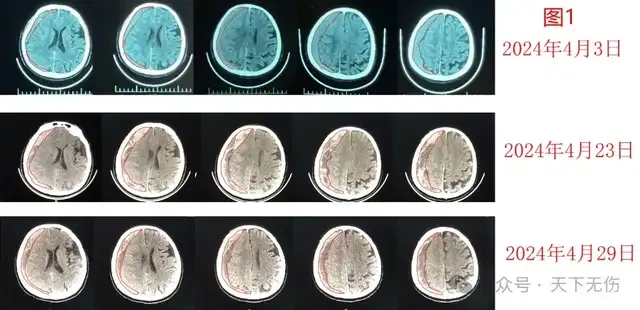

昨天,我向我在北京的師兄、修波教授匯報我收治的一例慢性硬膜下血腫患者的結果,他贊揚我做了大好事。修波是我國著名的脊柱脊髓專家,他是我碩士階段師兄,是神經外科先驅之一段國升教授的博士生,畢業(yè)后一度也是我的帶教老師。他從1990年代末就開始專注脊髓脊柱手術,尤其擅長腰骶椎的各種結構異常手術甚至是別人術后失敗的手術,手術量在該領域應該為最驚人的教授之一。由于盛名傳播,找他看病的患者多。他前幾天接診了L先生。L先生,71歲,在3月20日左右頭部受傷,當時的CT檢查只是硬膜下積液,幾乎沒有癥狀,也就沒有在意;4月3日頭部出現(xiàn)脹懵感,復查CT確診為右側慢性硬膜下血腫,近日有加重趨勢。修教授說關注我的朋友圈很久,愿意推薦患者給我,覺得我的方法是最好的。L先生上周一一早來我門診,剛開始還想拿著我的藥方回北京治療,我見他血腫不小,就勸他住院治療,并囑咐主管醫(yī)生必須復查CT。結果4月23日頭CT顯示血腫較4月3日明顯增大了,查體還發(fā)現(xiàn)他的左腿力量弱于右腿。我根據(jù)他的情況為他實施了藥物加頭頸淋巴按摩療法。不知是否擔心治療無效,L先生壓力很大,本來愛笑的他變得沉默寡言,笑容明顯減少。我問他癥狀有沒有變化,他一會兒說好像沒有變化,但一會兒又說好像治療2天后,就再也不覺得有頭部脹懵感了。我經常去安慰他不要緊張。今天下午復查CT,見他的血腫明顯減少了。他終于笑容燦爛。我第一時間將他的影像分析圖發(fā)給修教授(圖1)。平素嚴肅的、不輕易表揚師弟的師兄,給了我熱情洋溢的贊揚,讓我非常受用。當然,我更感謝他的支持和信賴。實際上,最近我接連收住院了包括L先生在內共5例慢性硬膜下血腫患者,他們都接受了藥物加頭頸淋巴按摩療法,但實際上根據(jù)患者不同情況,對于藥的劑量和應用的持續(xù)時間是有所區(qū)別的。例如,上周四出院的S先生,78歲,他本來在門診已經接受過2周激素治療,他的住院治療策略就是頭頸淋巴按摩,并再延續(xù)2周激素治療(圖2);L女士,78歲,也在門診接受過2周激素治療,因為在家勞作后血腫變化并不明顯,她對頭頸淋巴按摩非常敏感,每次按摩完后都惡心想吐,非常焦慮。針對她的治療策略是加強心理輔導,糾正她過于用力的按摩動作,同時強調要遵守一些注意事項,她的激素治療也只延續(xù)2周。結果住院治療1周就讓她的血腫明顯縮?。▓D3);Z女士,70歲,不僅有嚴重糖尿病,還有嚴重骨髓異常增生癥,由于長期口服該病的治療藥還導致嚴重的肝功能障礙和貧血,我在咨詢血液科專家、確定她可以應用地塞米松后,給她的治療方案就是保肝治療同時,使用阿托伐他汀鈣和激素,也加上頭頸淋巴按摩,并隨時準備撤除他汀。結果她對治療非常敏感,來門診時面色發(fā)黃、容貌晦暗無力,已經無法走路,使用輪椅推入,但治療2天后她精神轉好,可以下地行走。今日再看她,已經容光煥發(fā),像換了一個人。頭CT檢查顯示血腫明顯減少(圖4),今日是走著出院的?,F(xiàn)在病房里還有一例老年女性的慢性硬膜下血腫患者,來時也是病殃殃的,走路不穩(wěn),今天治療第4天,再去看她時已經可以自己走路去廁所和完成洗漱……我對她的康復充滿信心。4月27日,在北京舉辦的第17屆中國腦血管病大會請我做慢性硬膜下血腫藥物治療的專題演講,并請我展望該病診療的未來趨勢。我認為,慢性硬膜下血腫是一個發(fā)病隱匿,絕大多數(shù)患者癥狀輕微的疾??;它還是老年人特別高發(fā)的疾病,而老年人基礎情況復雜。因此制定慢性硬膜下血腫的治療策略不僅要以臨床癥狀體征和影像學表現(xiàn)為中心,更要考慮患者的年齡、基礎病、心理狀態(tài)、治療史、甚至經濟狀況和每個醫(yī)院的治療能力等。由于絕大部分患者癥狀輕微,而我們的他汀加藥物加頭頸淋巴按摩綜合治療的治愈率高達90%以上,在有外科手術保障安全的前提下,“以最小代價讓患者獲得最大收益”應該成為我們治療慢性硬膜下血腫的原則和努力去實現(xiàn)的目標。雖然國內外不少神經外科醫(yī)生認為慢性硬膜下血腫的新手術方式是該病的治療未來。但是,作為治療該病超過1千例的醫(yī)生,我見識過很多因為慢性硬膜下血腫手術導致的悲劇,也見識過多例接受大家推崇的術式卻無效的患者,經我調整治療方案治愈的手術后失敗或者復發(fā)的患者就超過一百多例,還總是聽到不少樂意跟我分享的同行說他們用我的方案也治好了他們的患者??粗业幕颊咭粋€個快樂地出院休養(yǎng),我覺得至少在天津,不幸得了這個疾病的患者,絕大部分都能在接受非手術治療后快樂治愈。專家介紹江榮才教授二級教授,主任醫(yī)師,博導,海河醫(yī)學學者天津醫(yī)科大學總醫(yī)院神經外科中心常務副主任,科副主任,NICU主任天津市131第一層次人才,天津市醫(yī)學會神經重癥分會首任主任委員,天津市醫(yī)學會神經外科副主任委員中華醫(yī)學會神經外科學分會委員、腦外傷學組副組長中國醫(yī)師協(xié)會神經外科醫(yī)師協(xié)會神經重癥專委會副主任委員國家創(chuàng)傷醫(yī)學中心顱腦創(chuàng)傷專業(yè)委員會副主任委員中國老年保健協(xié)會神經外科學創(chuàng)新與轉化分會首任會長擅長復雜重型腦外傷、腦出血及慢性硬膜下血腫的診療。是他汀治療硬膜下血腫的主要發(fā)明者,治療慢性硬膜下血腫患者超1000名,總治愈率約90%